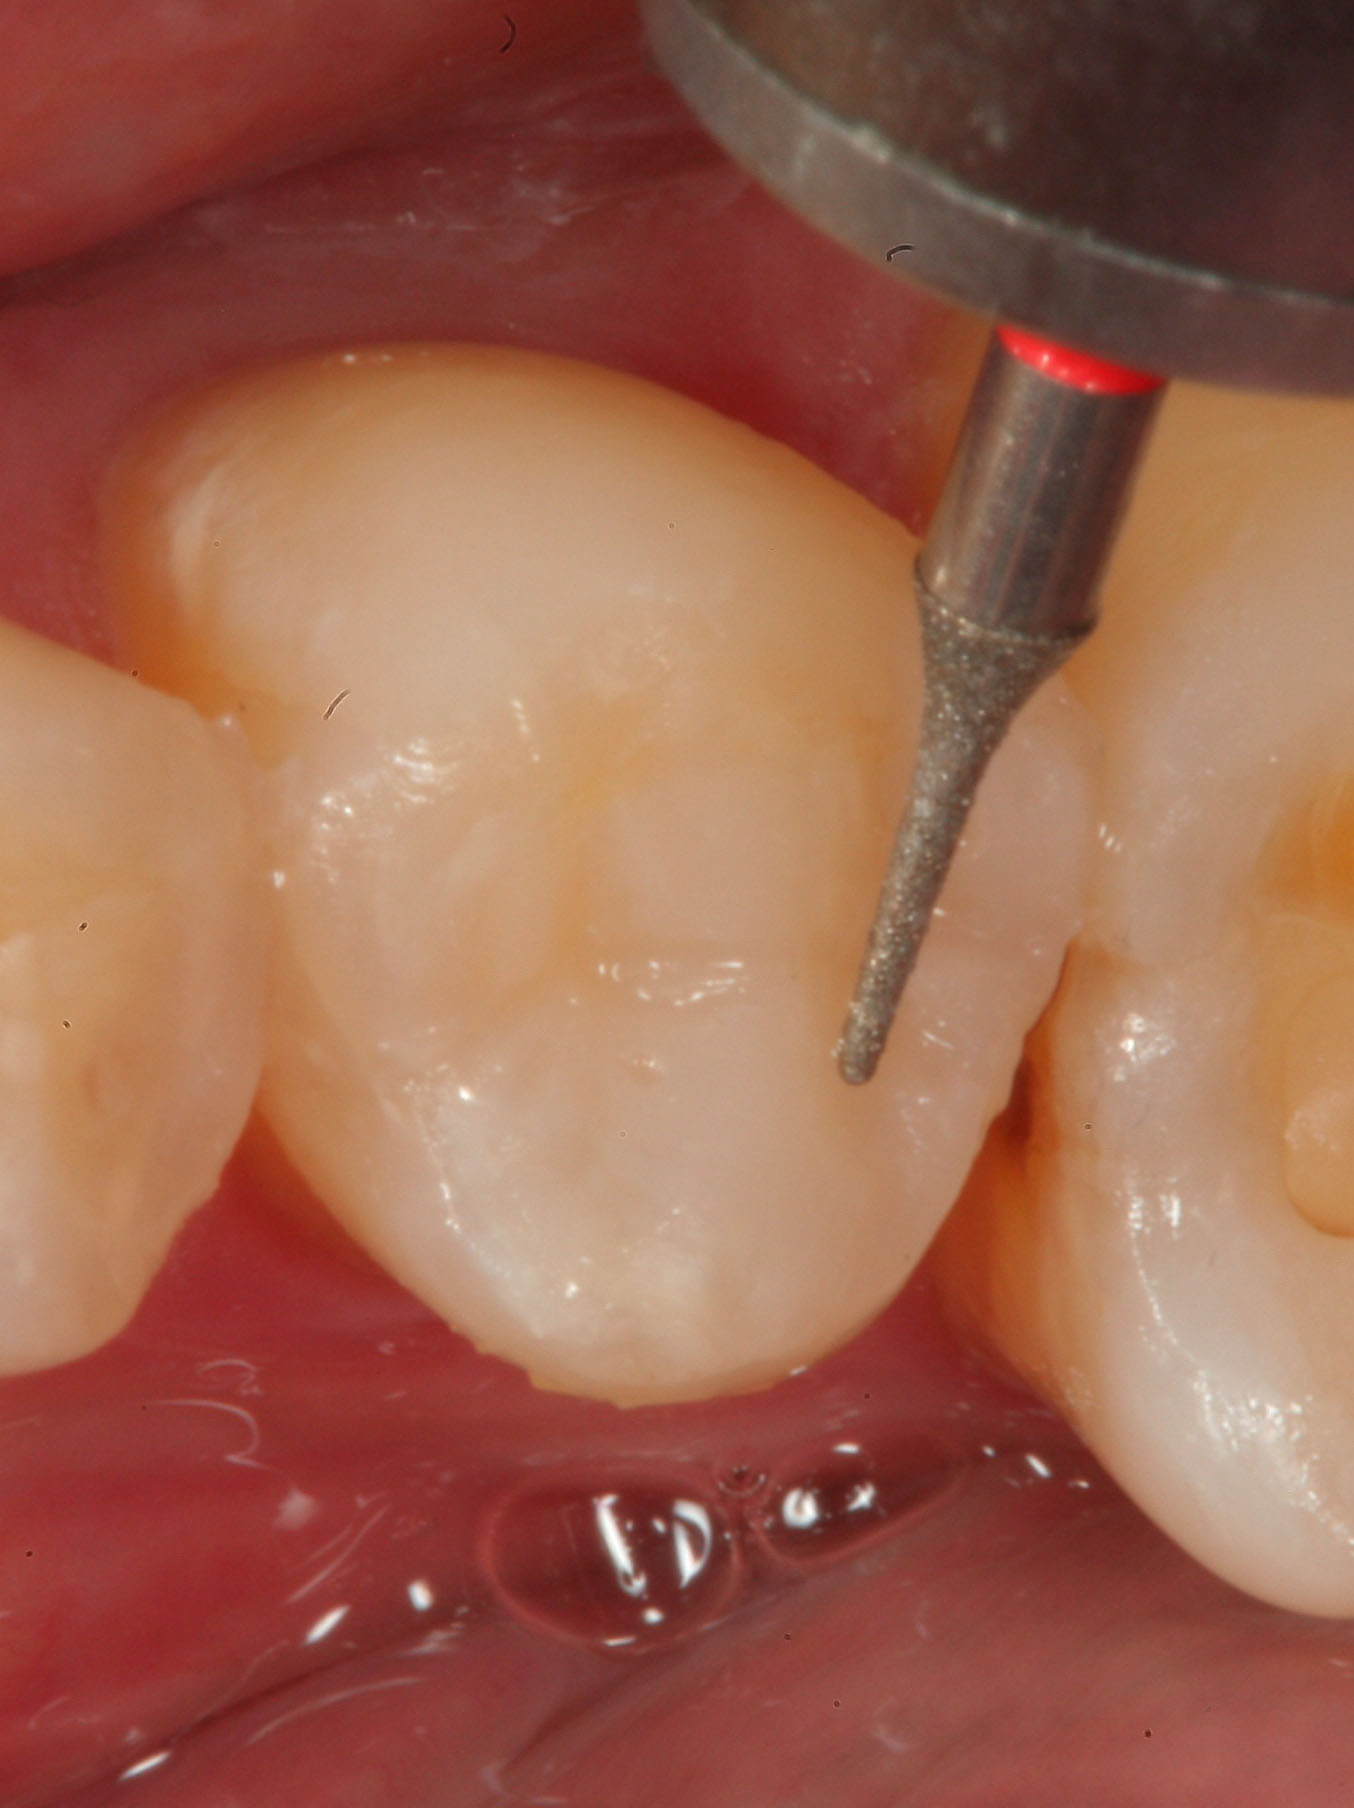

Fig 23. A needle-shaped diamond composite finishing instrument is used to refine the anatomic details before polishing the restoration.

Figure 23